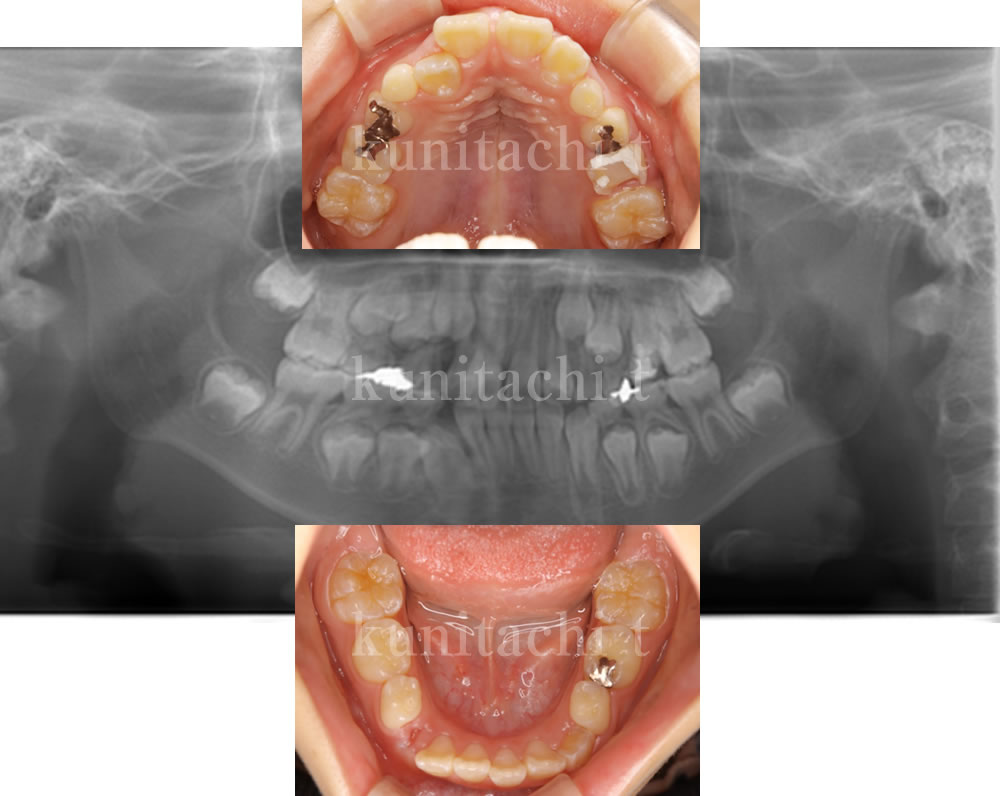

小児矯正で永久歯萌出スペース不足・叢生を改善した症例

永久歯の本数には問題ありませんでしたが、歯が並ぶためのスペースがやや不足しており、一部の歯が重なって生えている状態でした。このまま経過を見ると歯並びやかみ合わせに影響する可能性があるため、今後の成長も踏まえた治療をご提案しました。

【治療方針】

- 上下顎側方拡大

- 口腔周囲筋アンバランス改善(筋肉トレーニング専用ルーム)

- 呼吸改善

【使用装置】 ※1年半前後

- BB1

- uni.

- トレーナー